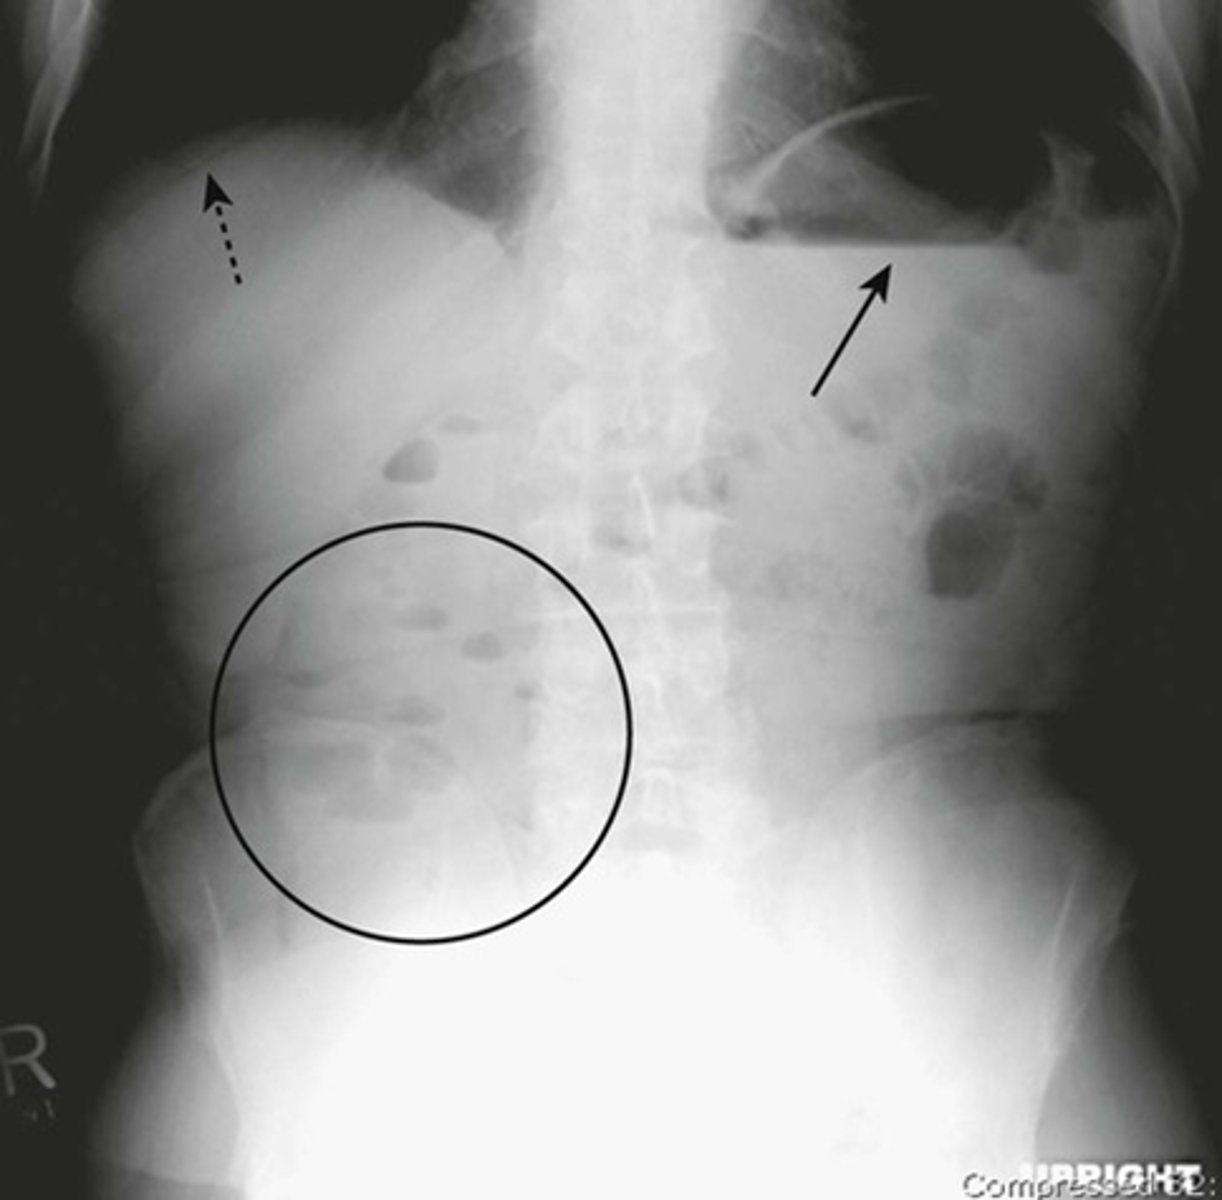

Normal supine abdomen

SOLID BLACK ARROW: small amount of air in about two or three loops of nondilated small bowel

DOTTED BLACK ARROW: air in stomach, always will have.

SOLID WHITE ARROW: air in the rectosigmoid colon.

DOTTED WHITE ARROWS: psoas muscles outlined by fat.